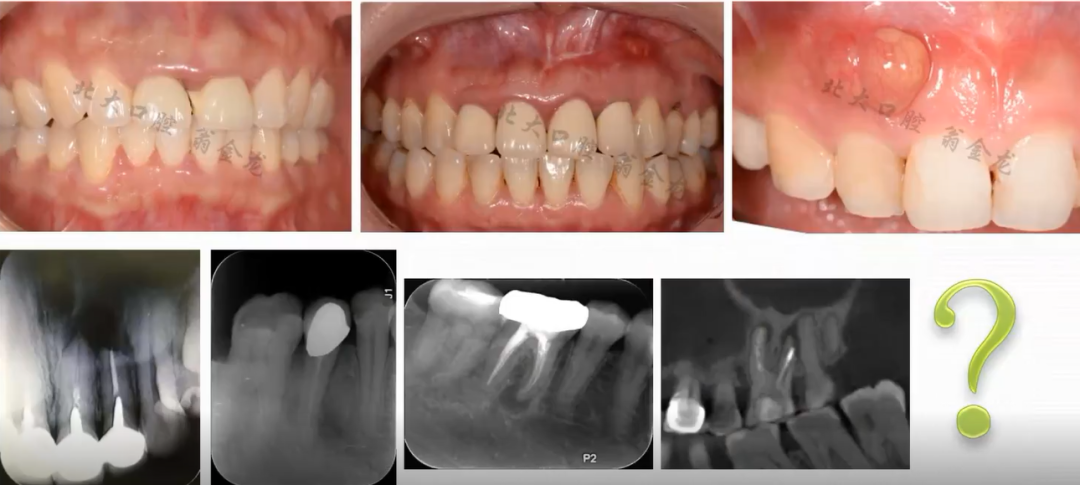

以下病例,您会考虑怎么做?

图片来源于训练营